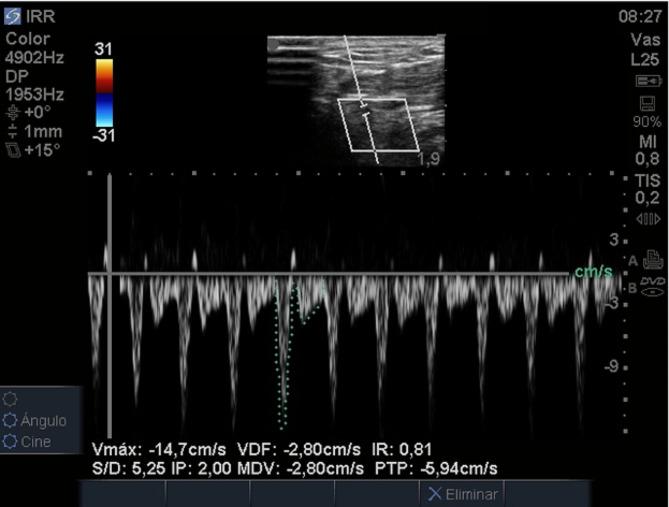

Ultrasound measurement of the radial resistance index (RRI) in the anatomical snuffbox has been proposed as a useful method for assessing the systemic vascular resistance index (SVRI). This study aims to establish the correlation between SVRI measured by pulmonary artery catheter (PAC) and RRI.

A cross-sectional study included all consecutive patients undergoing postoperative (POP) cardiac surgery with hemodynamic monitoring using PAC. Hemodynamic assessment was performed using PAC, and RRI was measured with ultrasound in the anatomical snuffbox. The Pearson correlation test was used to establish the correlation between RRI and SVRI measured using PAC. Hemodynamic behavior concerning RRI with a cutoff point of 1.1 (described to estimate under SVRI) was examined. Additionally, consistency between two evaluators was assessed for RRI using the intraclass correlation coefficient and Bland-Altman analysis.

A total of 35 measurements were obtained. The average cardiac index (CI) was 2.73 ± 0.64 L/min/m², and the average SVRI was 1967.47 ± 478.33 dyn·s·m²/cm. The correlation between RRI and SVRI measured using PAC was 0.37 [95% CI 0.045-0.62]. The average RRI was 0.94 ± 0.11. RRI measurements > 1.1 had a mean SVRI of 2120.79 ± 673.48 dyn·s·m²/cm, while RRI measurements ≤ 1.1 had a mean SVRI of 1953.1 ± 468.17 dyn·s·m²/cm (p = 0.62). The consistency between evaluators showed an intraclass correlation coefficient of 0.88 [95% CI 0.78-0.93], and Bland-Altman analysis illustrated adequate agreement of RRI evaluators.

For patients in cardiac surgery POP, the correlation between the SVRI measured using PAC and the RRI measured in the anatomical snuffbox is low. Using the RRI as a SVRI estimator for patients is not recommended in this clinical scenario.

有人提出,通过超声测量解剖学鼻烟壶处的桡动脉阻力指数(RRI)是评估全身血管阻力指数(SVRI)的一种有用方法。本研究旨在确定通过肺动脉导管(PAC)测量的SVRI与RRI之间的相关性。

一项横断面研究纳入了所有接受心脏手术后(POP)并使用PAC进行血流动力学监测的连续患者。使用PAC进行血流动力学评估,并在解剖学鼻烟壶处用超声测量RRI。采用Pearson相关性检验来确定RRI与使用PAC测量的SVRI之间的相关性。研究了RRI截止值为1.1(用于估计低于SVRI的情况)时的血流动力学行为。此外,使用组内相关系数和Bland-Altman分析评估了两位评估者对RRI评估的一致性。

共获得35次测量数据。平均心脏指数(CI)为2.73±0.64L/min/m²,平均SVRI为1967.47±478.33dyn·s·m²/cm。使用PAC测量的RRI与SVRI之间的相关性为0.37[95%CI 0.045-0.62]。平均RRI为0.94±0.11。RRI测量值>1.1时,平均SVRI为2120.79±673.48dyn·s·m²/cm,而RRI测量值≤1.1时,平均SVRI为1953.1±468.17dyn·s·m²/cm(p=0.62)。评估者之间的一致性显示组内相关系数为0.88[95%CI 0.78-0.93],Bland-Altman分析表明RRI评估者之间具有充分的一致性。

对于心脏手术后POP患者,使用PAC测量的SVRI与在解剖学鼻烟壶处测量的RRI之间的相关性较低。在这种临床情况下,不建议将RRI用作患者的SVRI估计值。